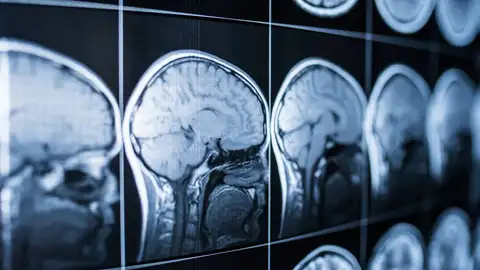

Un estudio ha demostrado que, con una herramienta de inteligencia artificial, se puede medir el envejecimiento del cerebro para prevenir el riesgo de deterioro cognitivo y el Alzheimer. El modelo ha predicho con un error absoluto promedio de 2,3 años las edades reales de los participantes.

Ahora, investigadores de la Universidad del Sur de California han desarrollado un modelo de inteligencia artificial que analiza resonancias magnéticas para calcular con precisión el deterioro cognitivo producido por enfermedades como el Alzheimer.

Para ello, los expertos escogieron a 4.681 participantes sin ninguna dolencia cognitiva a los que se les realizó una resonancia magnética. La IA escaneó estas imágenes y elaboró patrones de envejecimiento específicos del sujeto, para luego comparar las edades cerebrales biológicas con las edades reales de los participantes.

Así, a mayor diferencia entre los dos datos, más riesgo tendrían de desarrollar problemas cognitivos. Este modelo ha predicho con un error absoluto promedio de 2,3 años las edades reales de los participantes.